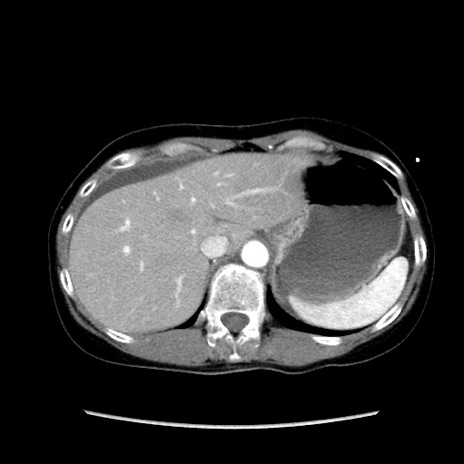

症例32(横断像)

【症例】40歳代 女性

【主訴】上腹部痛、嘔気・嘔吐

【現病歴】約9時間前頃から急に上腹部痛、嘔気、嘔吐が出現。改善しないため救急要請。

【既往歴】子宮頚癌(広汎子宮全摘術、放射線療法)、腸閉塞

【身体所見】腹部:平坦、軟、腸雑音亢進、上腹部を中心に腹部全体に圧痛あり。

【データ】WBC 8400、CRP 0.03